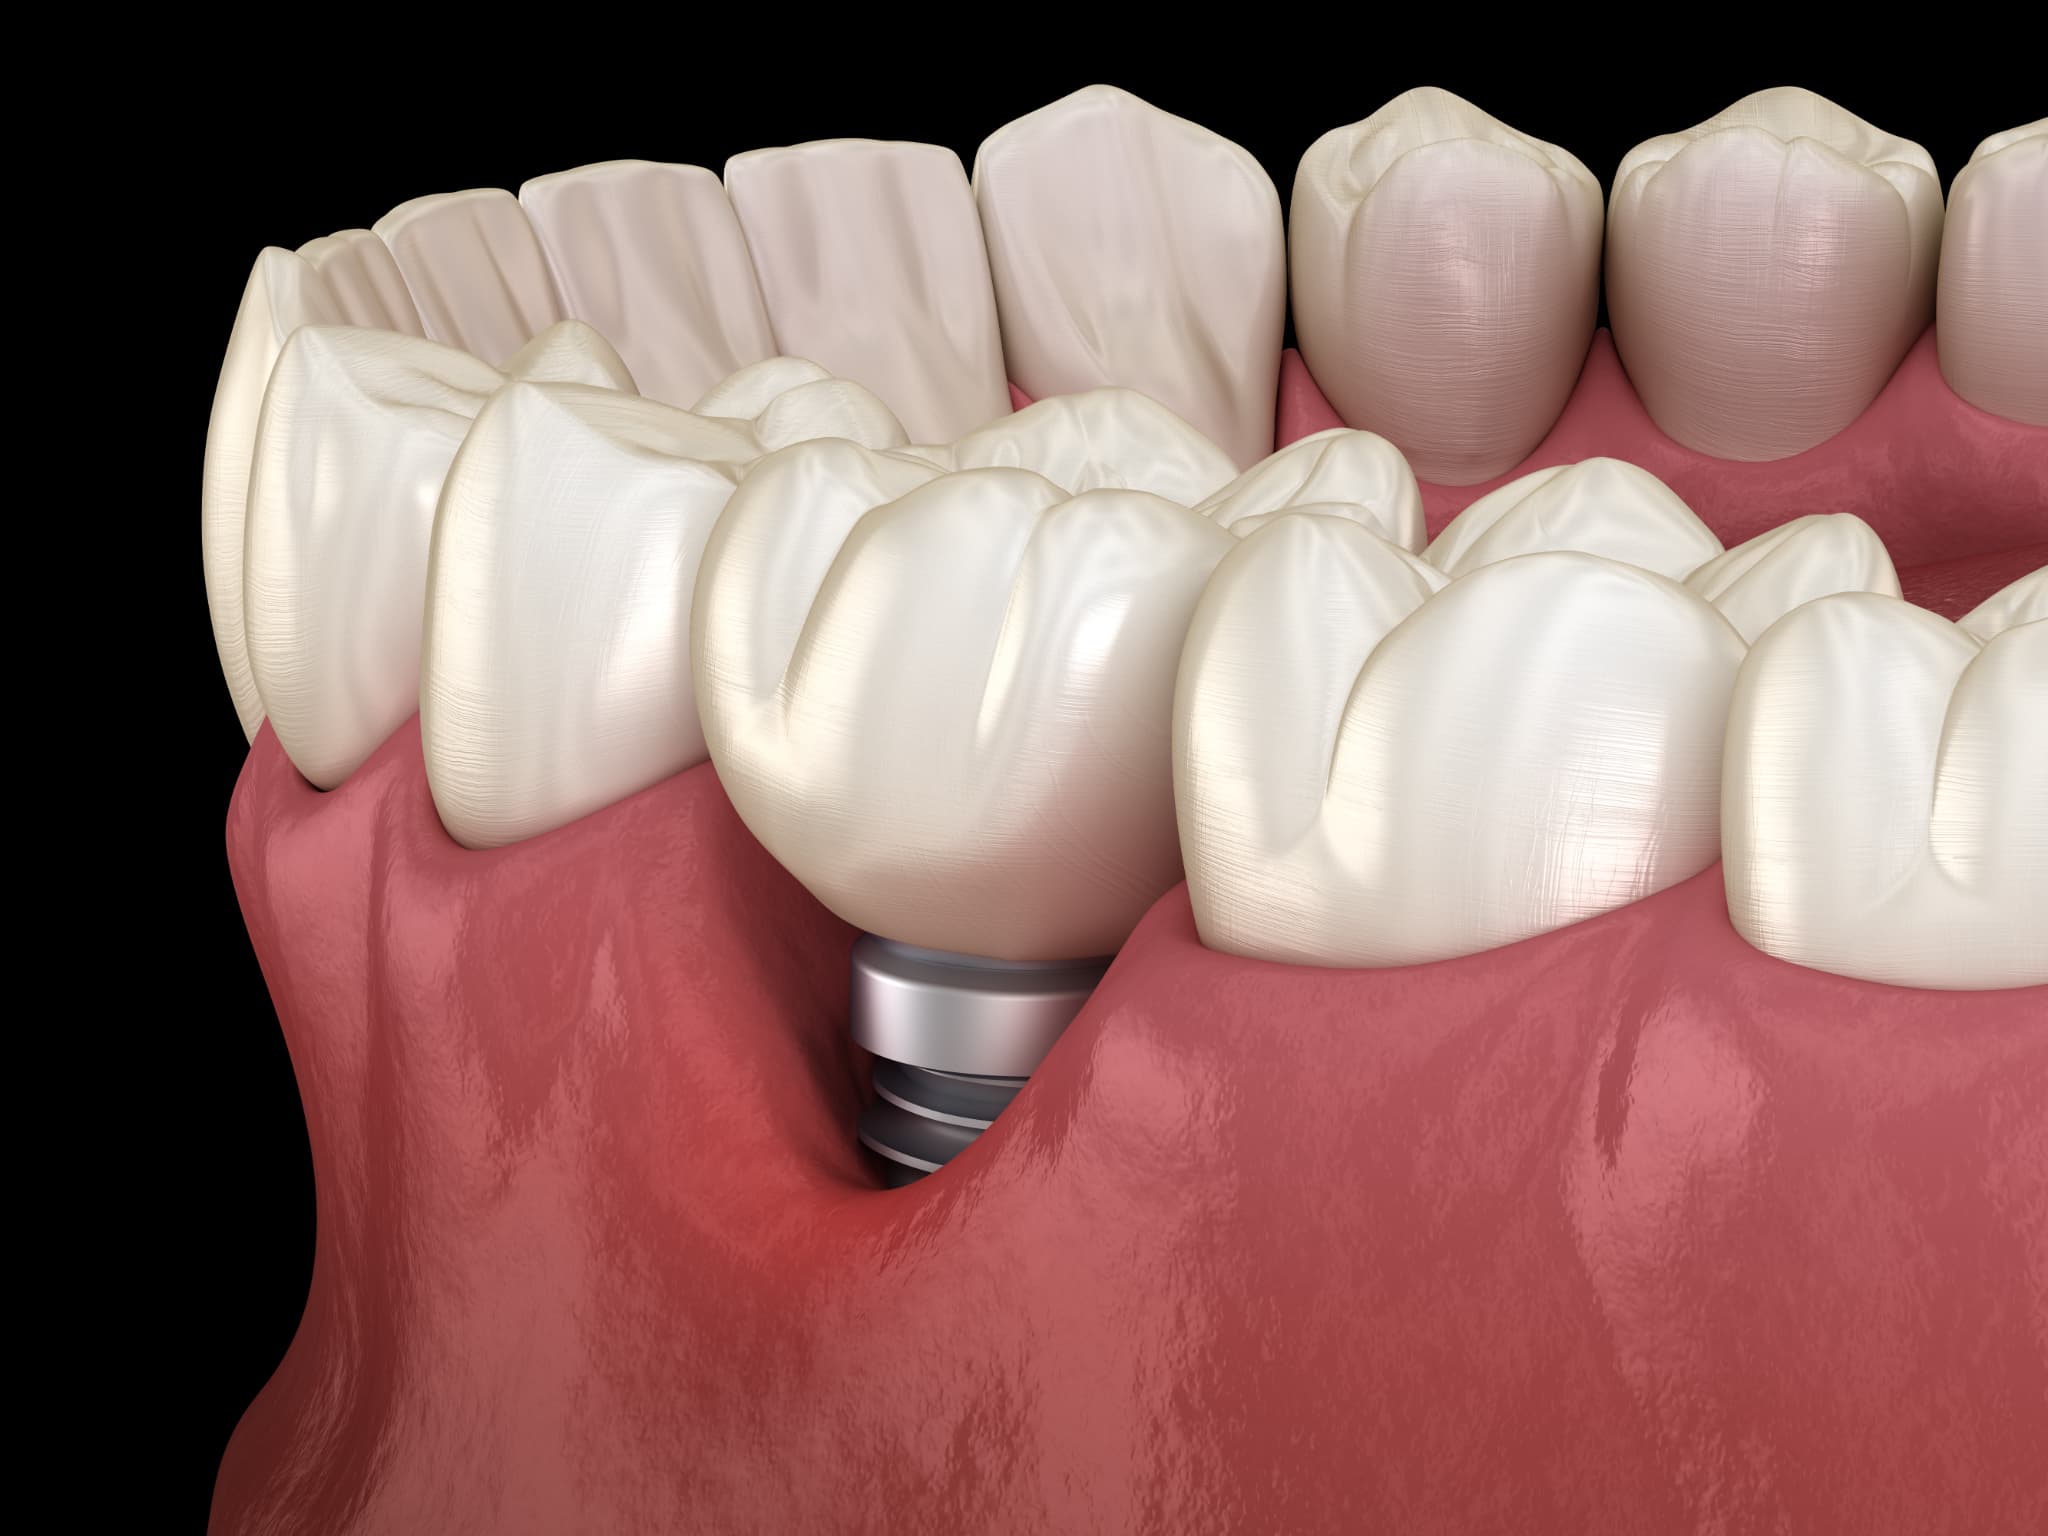

インプラント治療とは

インプラント治療は、顎の骨に人工歯根を埋め込み、その上に人工歯を装着することで機能と見た目を回復させる方法です。

この治療では、主にチタン製の人工歯根が使用され、骨と結合する性質を活かして安定した噛み心地を得ることができます。入れ歯やブリッジと異なり、周囲の歯への負担が少ない点も特徴です。また、自然な見た目に近づけやすく、審美面を重視する方にも選ばれています。

一方で、外科的処置を伴うため、術後のケアやメンテナンスが重要となります。適切な管理が行われない場合、歯茎の変色や炎症などのトラブルにつながる可能性があります。